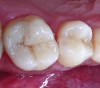

Figure 6. Amalgam is not usually bonded to the walls of the cavity preparation; thus, a space of several microns commonly exists between the restoration and the prepared surfaces. This leads to a potential for microbial invasion and secondary caries, as in this case of these defective amalgam restorations with recurrent decay.

Figure 6

Figure 7. The occlusal outline was extended only to include carious enamel, provide access to the carious dentin, and remove any residual amalgam staining.

Figure 7